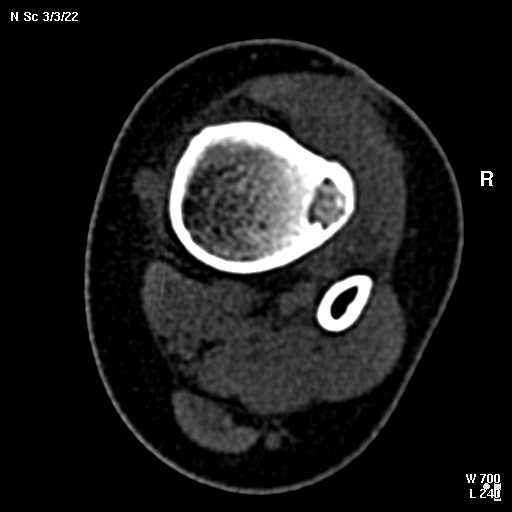

КТ изображения передаю на мой взгляд самые демонстративные. Их любезно записал коллега,

проводивший исследование в другом городе.

Прошу прощения за немного некоректную отправку КТ-снимков но по другому не получается :)

6